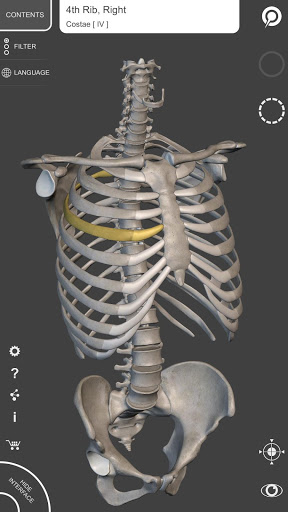

"Skeleton | 3D Atlas of Anatomy" là atlas giải phẫu thế hệ tiếp theo ở dạng 3D cung cấp cho bạn các mô hình giải phẫu tương tác có độ chi tiết cao!

Mỗi xương của bộ xương người đã được tái tạo ở dạng 3D, bạn có thể xoay và phóng to từng mô hình và quan sát chi tiết từ mọi góc độ.

HÌNH GIẢI PHẪU 3D CÓ ĐỘ CHI TIẾT CAO

• Hệ thống xương

• Mô hình 3D chính xác

• Bề mặt của bộ xương có kết cấu độ phân giải cao lên đến 4K